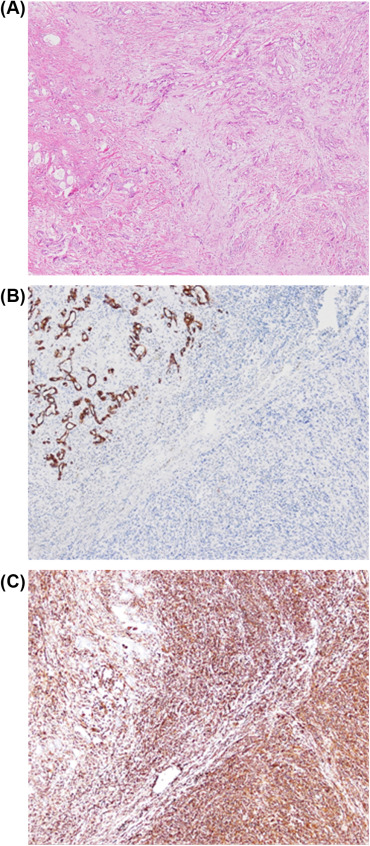

Adenocarcinoma is the most common type of malignant tumor generated in the gallbladder, whereas sarcomatoid carcinoma (also called carcinosarcoma) is rare [1]. The diagnosis of sarcomatoid carcinoma is generally made pathologically and requires the simultaneous presence of both malignant epithelial and mesenchymal components. Immunohistochemically, the epithelial component is positive for cytokeratin and the mesenchymal component is positive for vimentin [2]. In a meta-analysis of sarcomatoid carcinoma, adenocarcinoma was found to be the most common pathology in the epithelial component, followed by mixed adenosquamous cell carcinoma and squamous cell carcinoma. In the mesenchymal component, spindle cell pathology occurred most frequently followed by combined spindle cell and chondroid features, and osteoid histology [3].

Cholecystectomy and segmental hepatectomy of segments S4b and S5 were performed. An 8 cm, friable gallbladder mass had grown outward and involved the liver (Fig. 3). Pathologically, the tumor was a sarcomatoid carcinoma in Stage III (Fig. 4). The surgical margin was free of vessel or cystic duct invasion. The tumor had an adenocarcinoma component with some glandular structures and showed positive staining for cytokeratin (AE1/AE3) and a sarcoma component with spindle cells staining positively for vimentin.

Figure 4. (A) Sarcomatoid carcinoma of the gallbladder. Immunohistochemical staining showing (B) cytokeratin-positive epithelial component; (C) vimentin-positive sarcomatous component. |